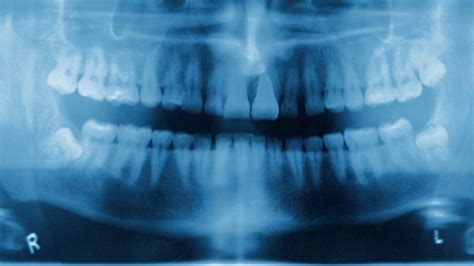

How dangerous is teeth whitening? - BBC News